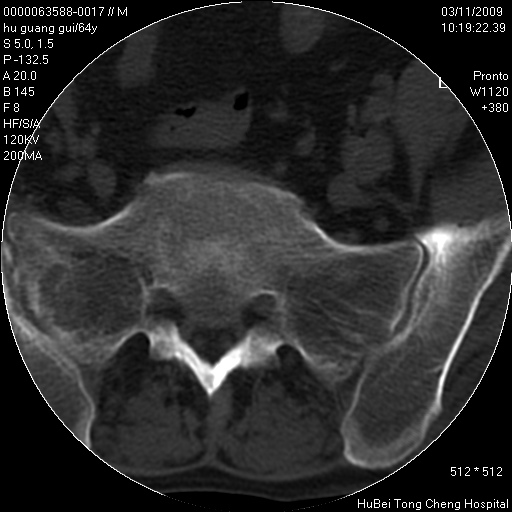

患者 男,64岁。腰痛十余天。(临床未提供其他病史)

临床诊断:腰痛原因待查(腰椎间盘突出症?)。

腰椎间盘ct轴位平扫(层厚5mm,层距4mm),图像如下:

右侧骶骨侧块骨侵蚀,骶髂关节骨性关节面破坏,并见软组织肿块,考虑骨转移瘤可能,进一步检查。

2.右侧骶骨侧块骨侵蚀,骶髂关节骨性关节面破坏,并见软组织肿块,考虑:脊索瘤,骨转移瘤可能,进一步检查。

1)腰椎退行性变,l4—5椎间盘膨出。2)骶骨右侧块骨转移瘤可能,3)水平骶椎。建议作一步检查。